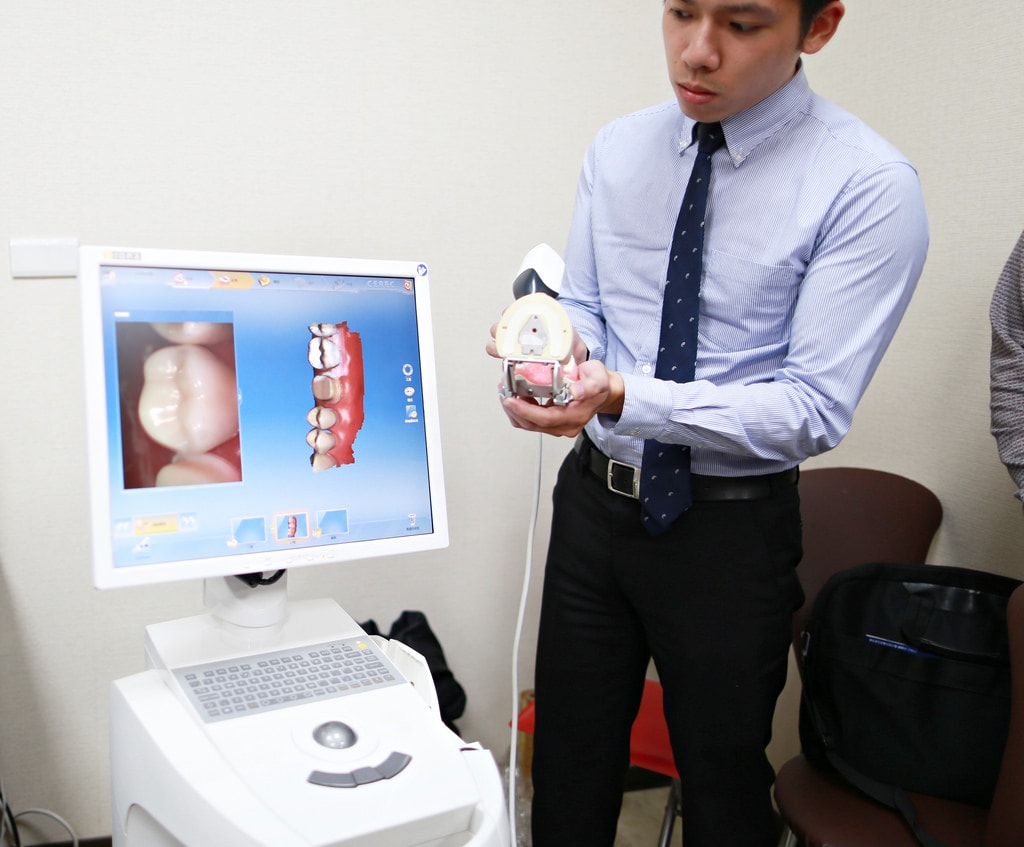

不得不說悅庭牙醫的所有醫療器材真的很棒,這台是CEREC 3D齒雕數位取像儀是最新引進的

這台最主要是植牙植進去人工牙根後需至少三個月後才可以做假牙,這時候就會使用這台機器

CEREC 3D齒雕數位取像儀是臨床使用的全瓷牙高科技設備,擁有自動電腦運算科技、細緻的光學影像技術、精確的研磨製造程序

能在一個診次完成美觀的全瓷修復體;病患不需戴上臨時牙套,不需多次約診與等待一週,當天立即完成高品質的全瓷修復治療

輕巧的CEREC 3D鏡頭,可於病患口內拍攝立體影像,立即取得精確的口內數位模型

進行後續的軟體設計,杜絕傳統翻模誤差,大幅節省臨床時間,提升修復體密合度

CEREC 3D軟體有非常方便的使用者介面,使用者透過3D鏡頭對治療區域取像後,軟體能夠立即將影像轉換成3D無死角的立體虛擬模型

清楚呈現病患口內真實修型的狀況,再運用軟體輕鬆快速的完成修復體的設計

在軟體上就能預先看到咬合的情況直接調整,能夠精準控制咬合高度

且咬點位置都能夠利用CEREC 3D 強大的軟體來控制,大幅降低臨床調整時間

數位印模能提供比傳統印模更精密的數位模型,杜絕傳統印模經常發生的許多誤差